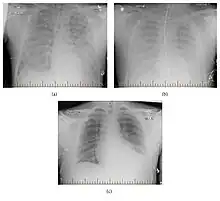

Progression of hantavirus pulmonary syndrome